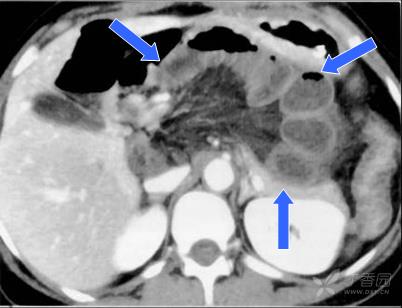

2 左側十二指腸旁疝的CT表現

CT特征為左上中腹一堆互相擁擠的小腸聚集于一異常囊袋樣腫物內,其內腸管顯示擴張、通常以積液為主,腸管位于Treitz韌帶左側,在胃和胰之間,遠段小腸和橫結腸在其下方。供應疝囊內小腸的血管擴張、聚集、拉直伸展入疝囊內。疝囊頸的前界可顯示腸系膜下靜脈和左結腸動脈。遠側腸管正常或萎陷。